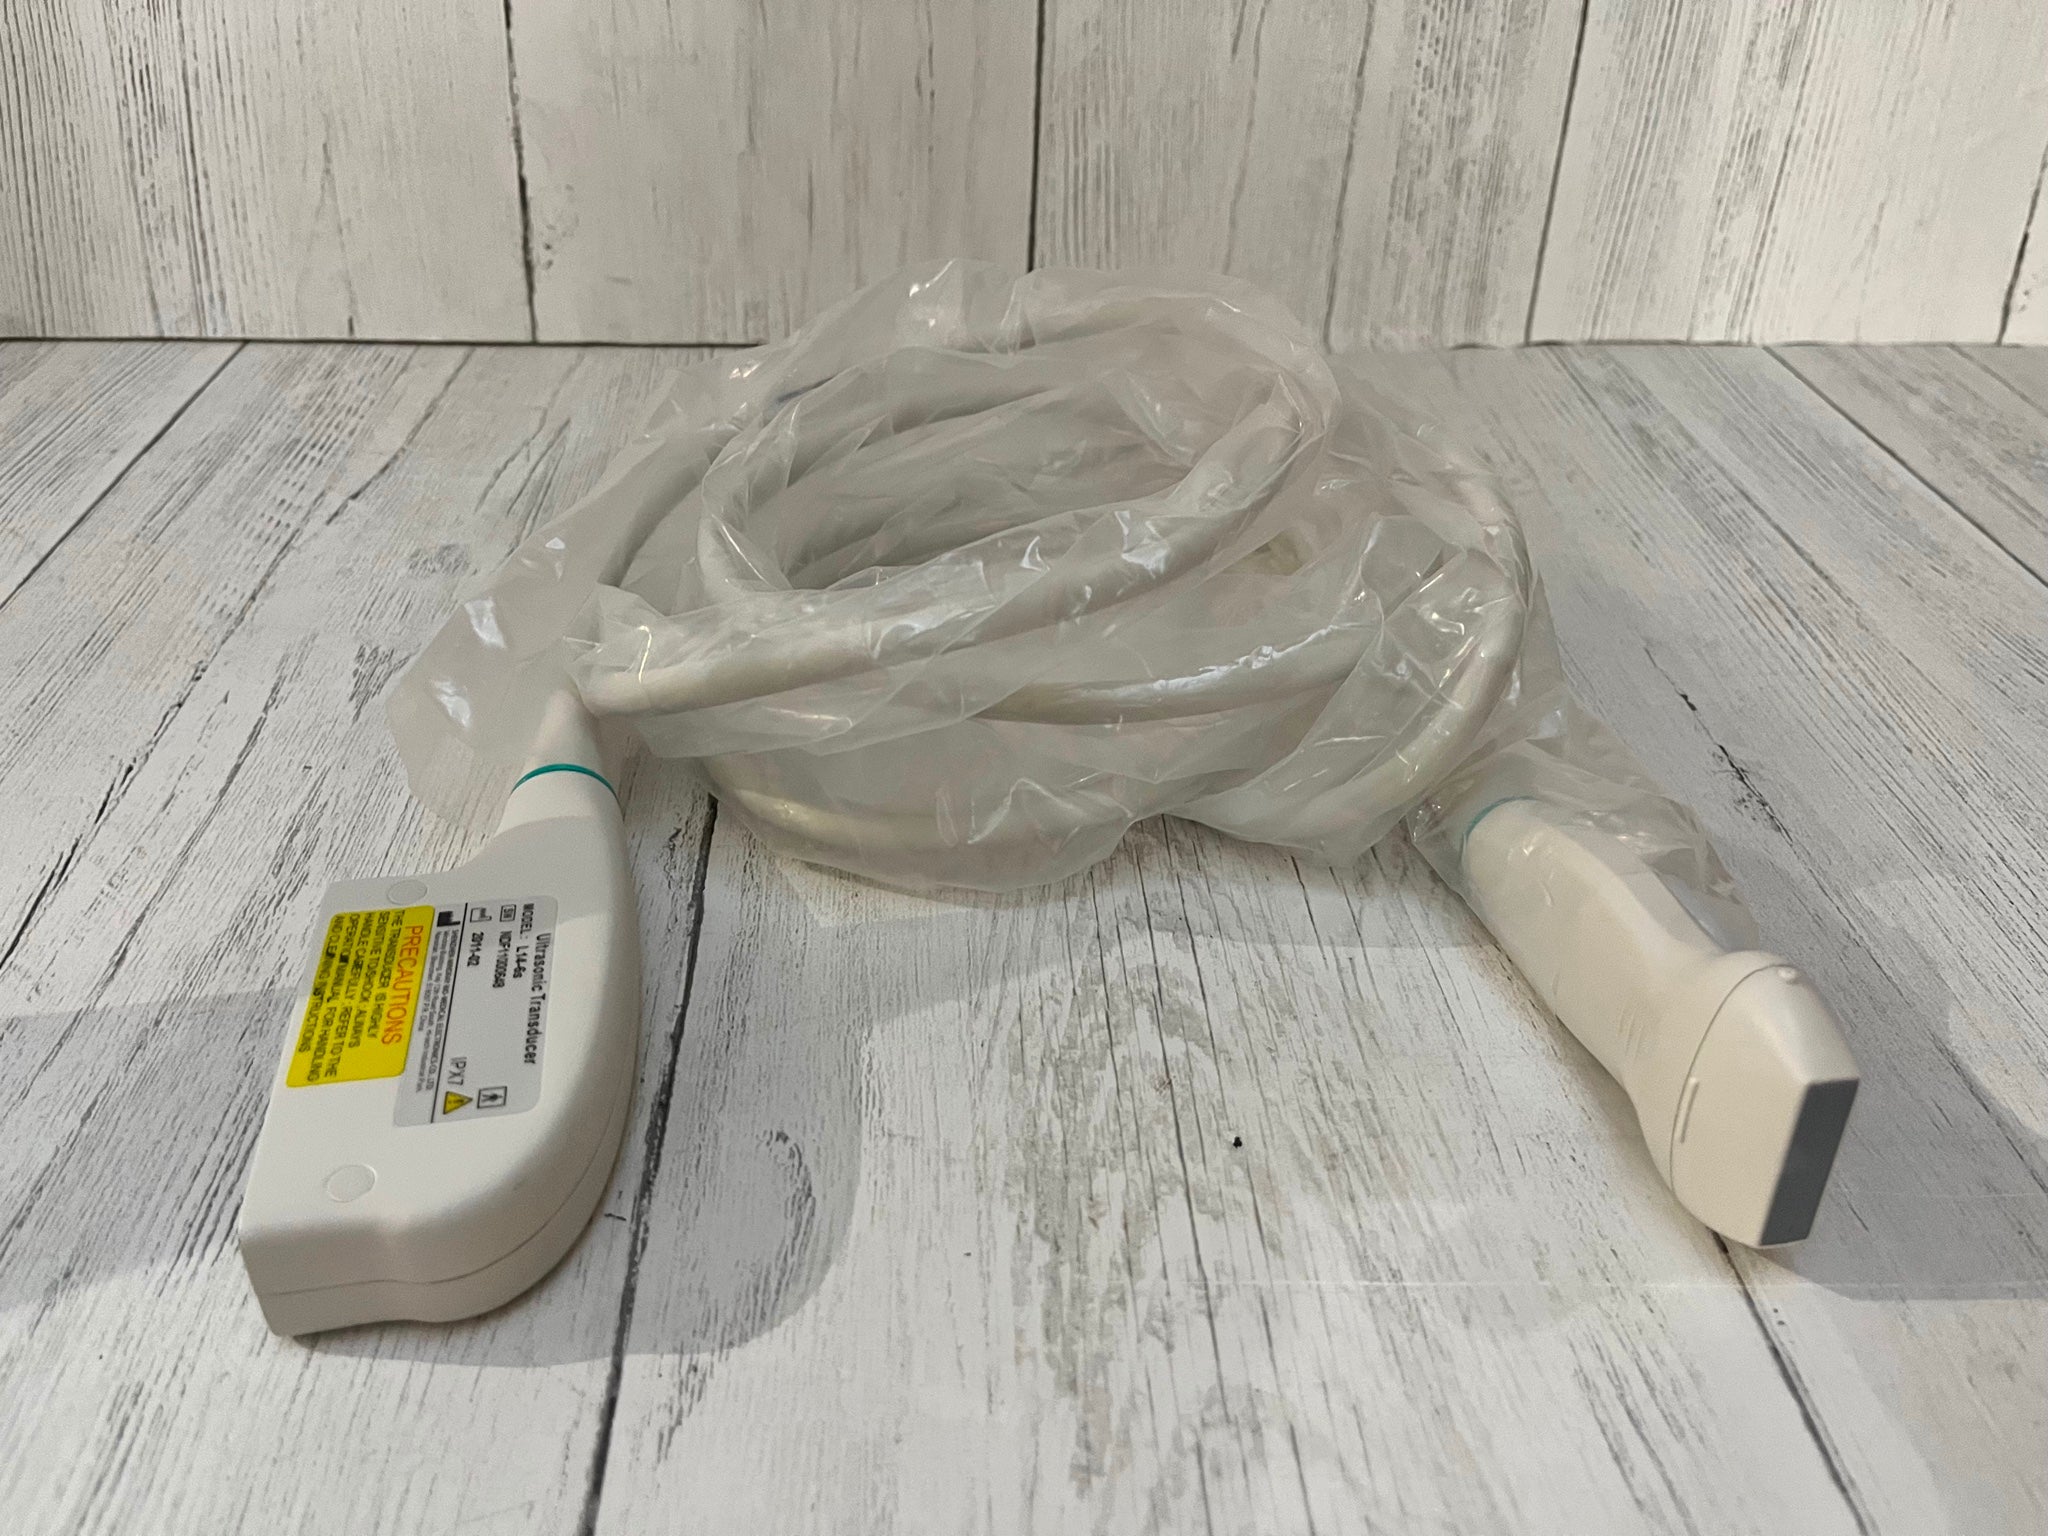

Mikrokonvexe Sonde |

1 |

Linearer Bauch |

1 |

Konvexe Sonde |

1 |